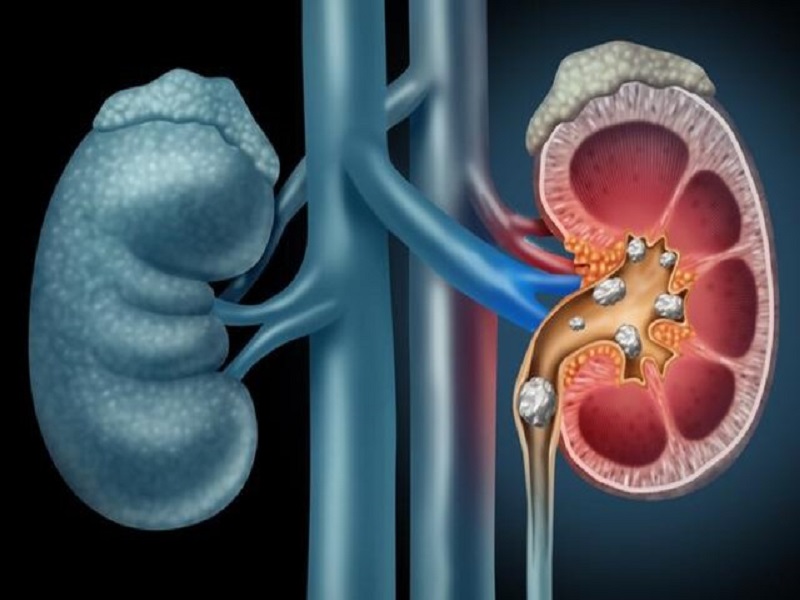

چه خوراکیهایی کلیهها را سنگساز میکند؟

به گزارش خبرگزاری تابناک کرمانشاه به نقل از ایسنا دکتر عبدالله سعادتفر جراح و متخصص کلیه و مجاری اداری با بیان اینکه سنگ کلیه هم باعث ایجاد دردهای بسیار شدید شده و هم به کلیهها که از حیاتیترین ارگانهای بدن است آسیب میزند، گفت: رژیم غذایی سالم، ورزش و داشتن تحرک و مصرف مایعات کافی راه نجات از سنگهای کلیوی است.

وی با بیان اینکه هر کلیهای که یک بار سنگ ساز شده امکان سنگ سازی مجدد دارد، عنوان کرد: برای جلوگیری از این امر باید عواملی که باعث تشکیل سنگ کلیه میشود را محدود کرد.

وی ادامه داد: توصیه ما به افرادی که دارای سنگ کلیه هستند این است که آب زیاد بنوشند. همچنین با مراجعه به پزشک و تجویز و مصرف داروهایی که به دفع سنگ کلیه کمک میکند میتوانند نسبت به دفع سنگ کلیهشان اقدام کنند و در مرحله آخر چنانچه سنگ دفع نشد برای آنها از اقدامات کمک جراحی استفاده خواهد شد.